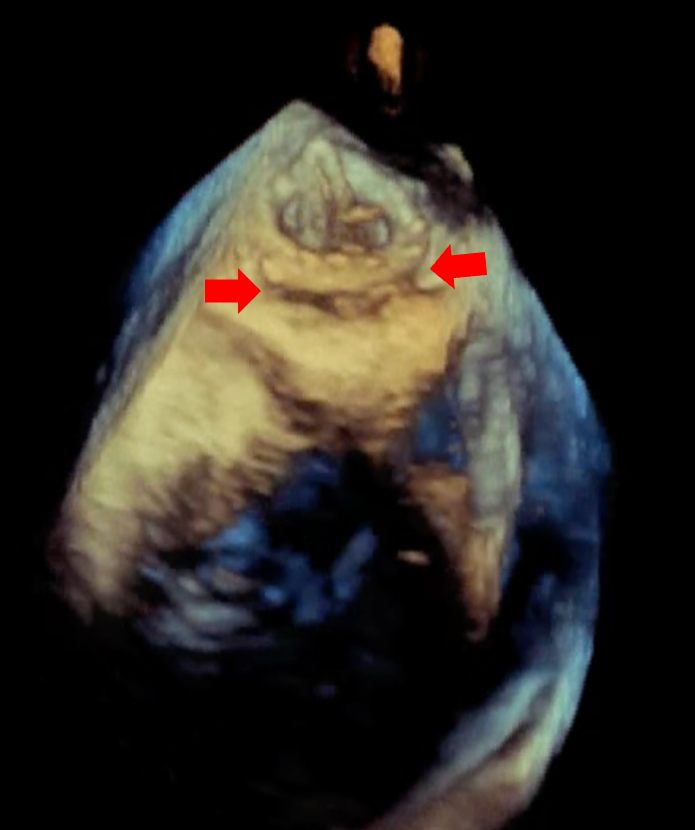

Echocardiography showed severe MR due to PVL with normal biventricular function. No vegetation or perivalvular collection was noted, and the other valves were normal. Transesophageal echocardiography showed a large PVL of the prosthetic mitral valve with valve dehiscence (Figure, Video 1). Coronary angiogram showed complete occlusion of the right coronary artery (RCA). Left ventricular angiography showed Seller grade 4 MR (Video 2) with a relatively small atrium.